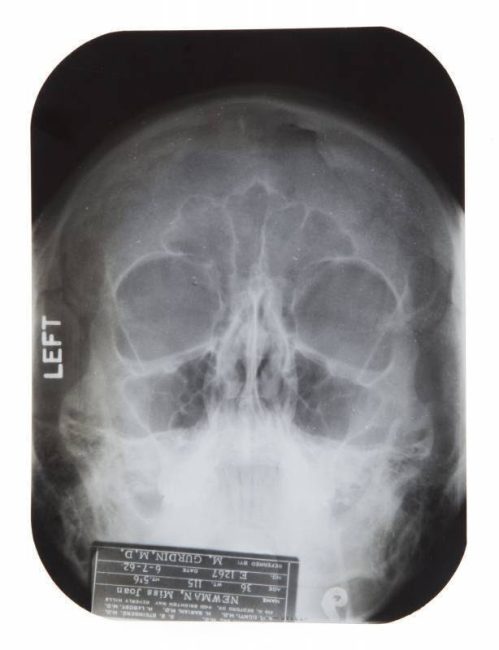

However, the files sold at Julien’s also included nasal X-Rays from the office of Drs. Conti and Steinberg, dated June 7, 1962, when Marilyn injured her nose after a fall in the shower. The X-Rays were labelled ‘Joan Newman,’ a pseudonym Marilyn used to protect her privacy. Fortunately, her nose was not fractured.